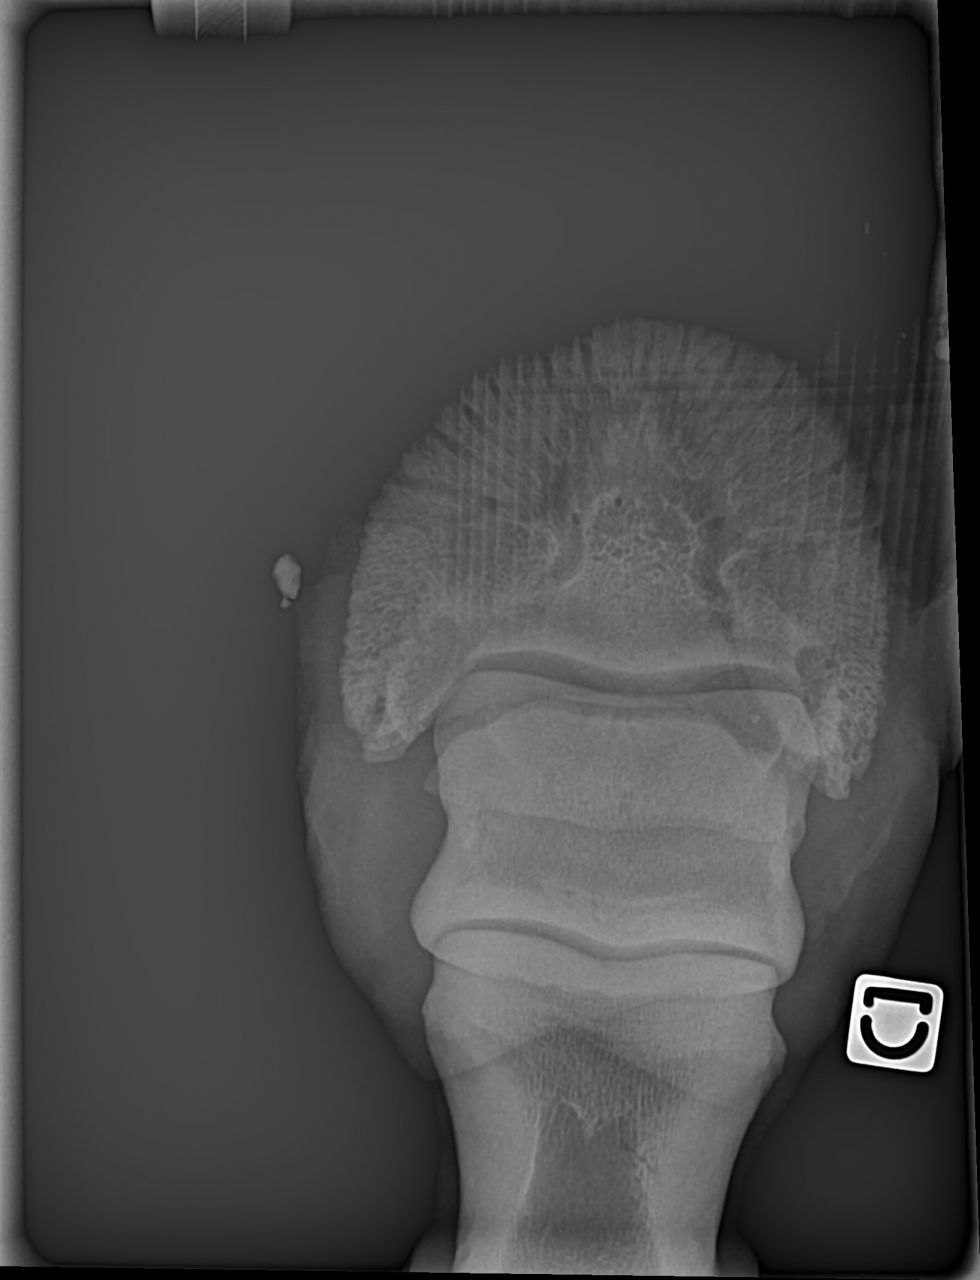

| Dire merci | les premières radios sont de juillet 2012 Voici les radios de l'antérieur droit fin septembre 2012 ![]() et celles de l'antérieur gauche ![]() ![]() |

Déconnecté | ben oui en voyant les radios, je me suis dit ostéïte direct. d'ailleurs elles sont assez impressionnantes. l'ostéïte a un caractère assez definitif,l'os ne peux pas se reminéraliser. les anti inflammatoires, c'est pour eviter qu'il y a ai une nouvelle infection qui déminéralise encore plus. quant à le remonter ....vu tes radios ... il faut imaginer que ses phalanges sont devenues aussi légère que de la roche volcanique pleine de trous ... au moindre choc, il va souffrir, et il risque des fissures de fatigue et de traumatisme aussi ... franchement, tes radios sont pas très encourageantes :S |